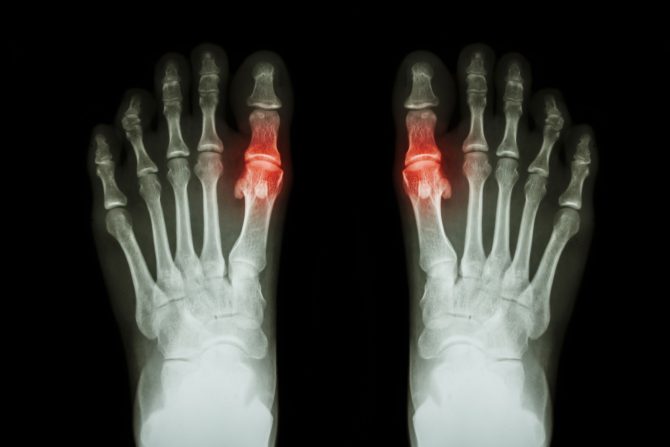

Metatarzofalangealni zglob povezuje kosti prstiju sa kostima stopala. Metatarzalne kosti su duge kosti koje povezuju srednje i zadnje stopalo sa prstima, a između glava metatarzalnih kostiju i dna proksimalnih falanga (kosti prstiju) nalaze se metatarzofalangealni zglobovi. Ovi zglobovi, poznati i kao MTP zglobovi, okruženi su tankom zglobnom kapsulom i imaju ligamente koji ih podržavaju. Poznati su i kao zglobovi velikog prsta.

Giht - Giht je oblik artritisa koji može da utiče na stopalo, posebno na prvi metatarzofalangealni zglob. Kada u telu ima previše mokraćne kiseline, to može dovesti do stvaranja bolnih kristala u zglobovima. Simptomi napada gihta su iznenadni, jak bol, crvenilo, otok i toplotu nožnog prsta.